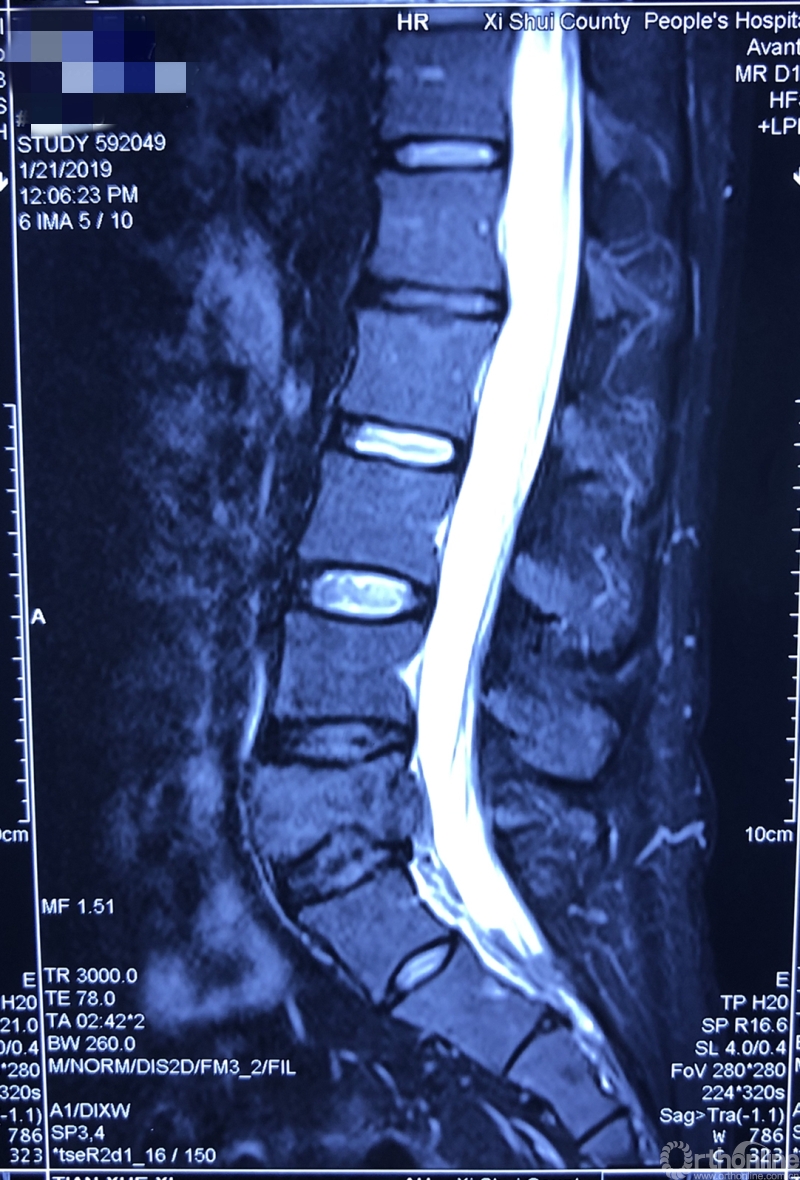

据介绍,患者为39岁男性,在一年前开始出现腰部反复疼痛的症状,休息下后疼痛还可以缓解,当时并未引起患者重视。过年后感觉疼痛加重,赴当地医院检查。核磁共振显示腰椎上长了一个鹅蛋大小的肿瘤,不偏不倚地侵蚀在第五节腰椎上,正是腰椎和骨盆连接部位附近。于是患者来同济医院骨科就诊。

就诊前CT